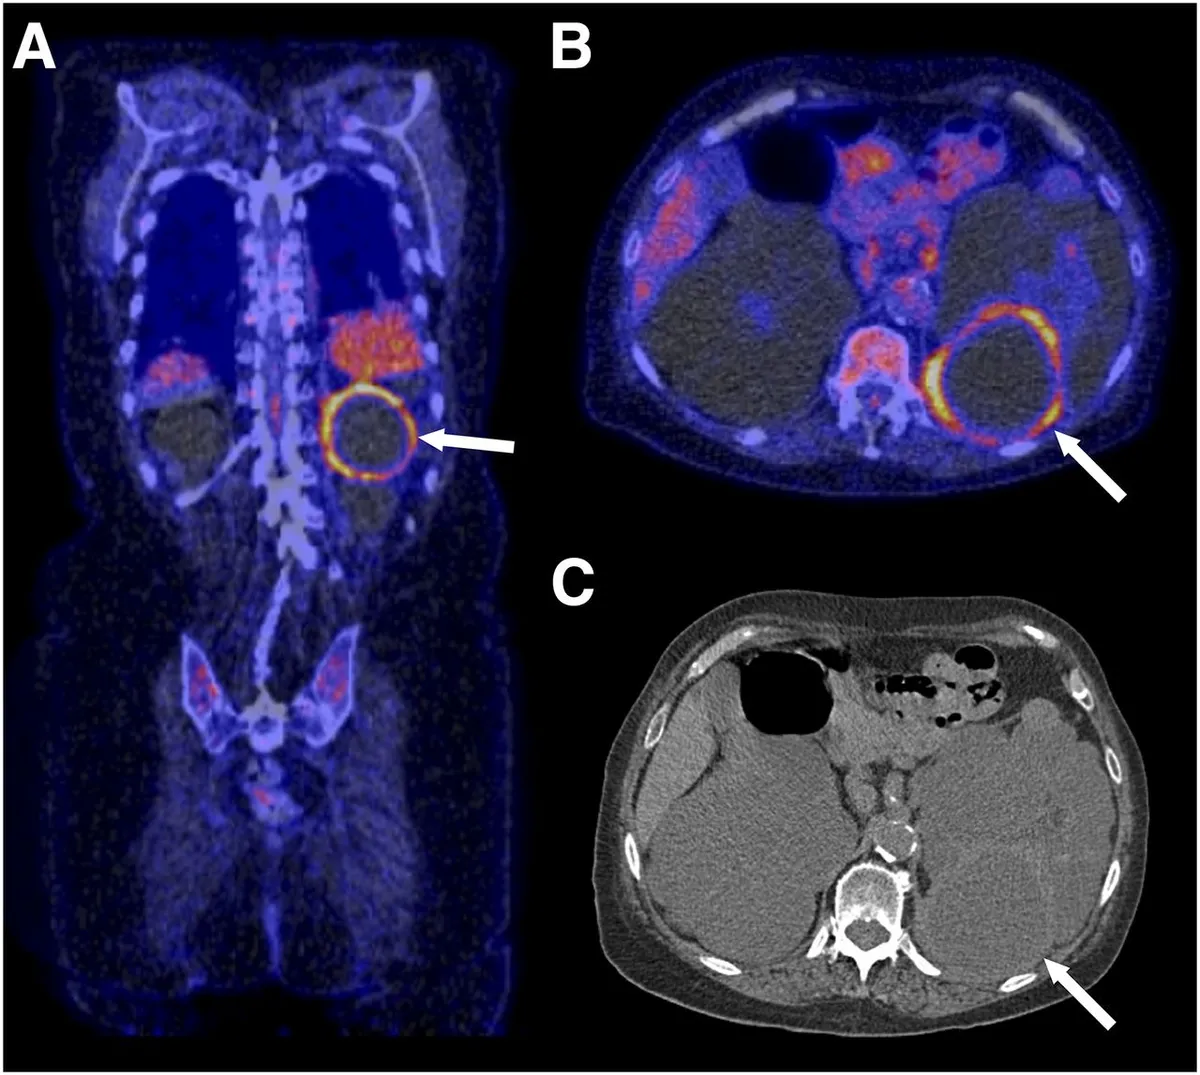

Você sabe quando suspeitar de infecção de cisto em pacientes com DRPAD? Nem toda febre é pielonefrite! Veja os achados clínicos e radiológicos que ajudam no diagnóstico, escolha os antibióticos com melhor penetração e evite falhas terapêuticas. Post indispensável para nefrologistas que lidam com infecção renal em pacientes com múltiplos cistos!

Valkercyo Feitosa